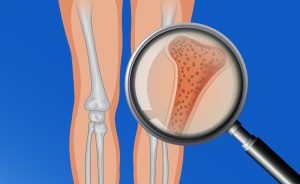

La fisioterapia como ayuda para mejorar la osteoporosis.

“El silencio es el ruido más fuerte, quizá el más fuerte de todos los ruidos” Miles Davis. En la siguiente entrada del blog vamos a